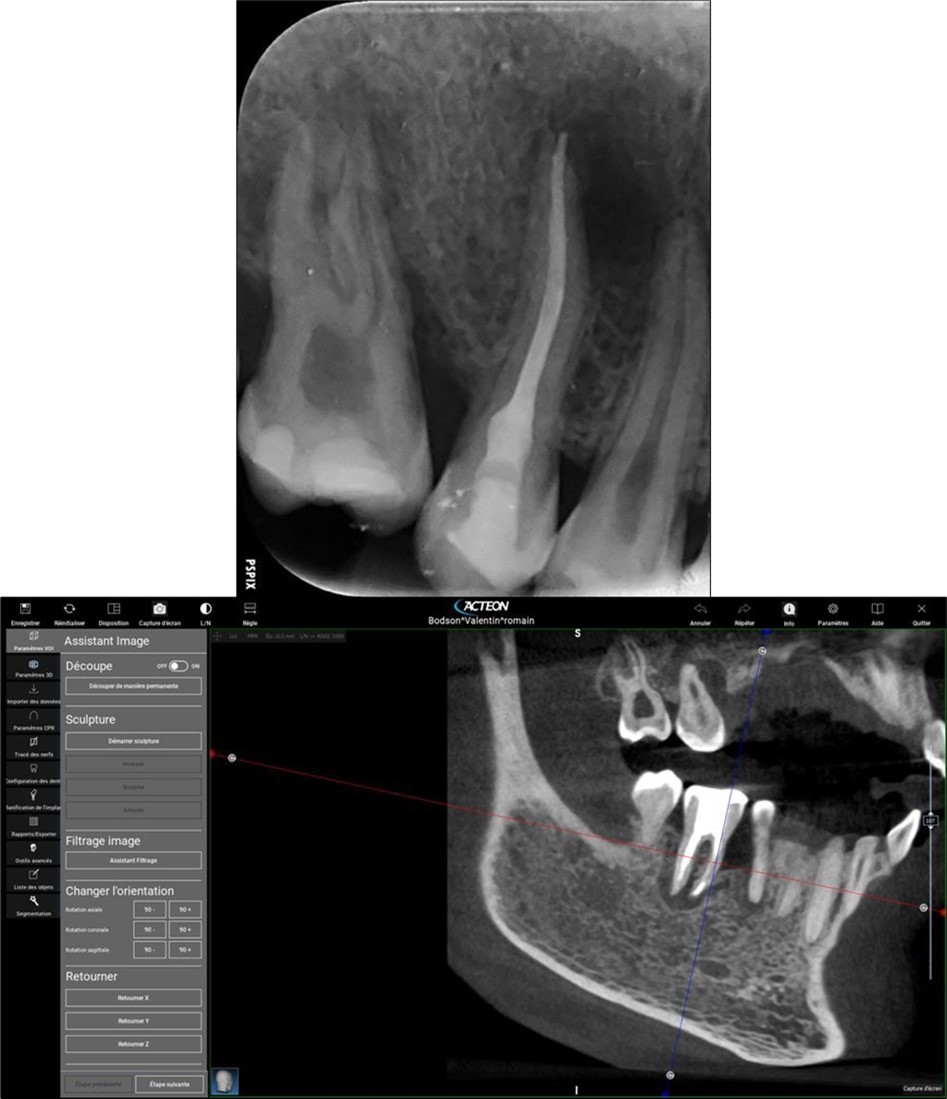

Periapical radiography (phosphorus number 2 plaque and X-MIND® Unity; Acteon) and cone-beam computed tomography (X-MIND® 3D; Acteon) (80 × 80, 150 Micron) were performed and showed periapical lesions on teeth 14, 15, 16, 24, 25, 26, 35, 36, and 46, as well as advanced endo-perio lesions on teeth 26 and 16. orthopantomogram (X-MIND® 3D; Acteon) and bitewings (phosphorus number 2 plaque and X-MIND® Unity; Acteon) also showed wide pulp chambers and roots canals. Figure 1, Figure 2

Figure 1.1 and 2 show a wide pulp chamber, root canals, and several restorations.

Figure 2.2. 3, 4, and 5 show periapical lesions on teeth 15, 16, 24, 25, 26, 35, 36, and 46.